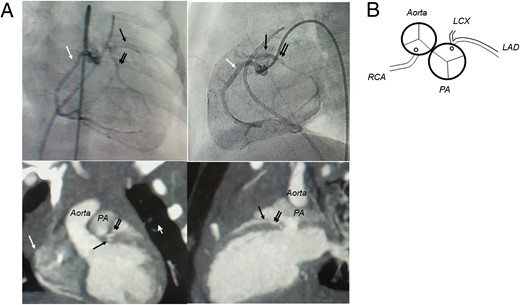

A 1-month-old female was admitted to our institution with high fever, cough and poor feeding caused by respiratory syncytial virus infection. Two-dimensional and color-flow Doppler echocardiography demonstrated a grossly hypokinetic and dilated left ventricle with mild-to-moderate mitral regurgitation, in addition to reversal of flow from the anomalous left coronary artery into the pulmonary artery (PA) that constituted a left-to-right shunt. Cardiac catheterization and computed tomography coronary angiography showed the single right coronary arising from the aorta and retrograde filling of the left coronary artery with a very short main coronary trunk that originated from the rightward posterior sinus of the PA (Fig. 1).

(A) Preoperative cardiac catheter angiography, contrast CT and (B) the schema of the coronary pattern. The aorta is located right and posterior to the PA, and the left coronary artery with a very short main coronary trunk originates from the rightward posterior sinus of the PA (LAD: left anterior descending artery, black arrow; LCX: left circumflex artery, double arrows; RCA: right coronary artery, white arrow).